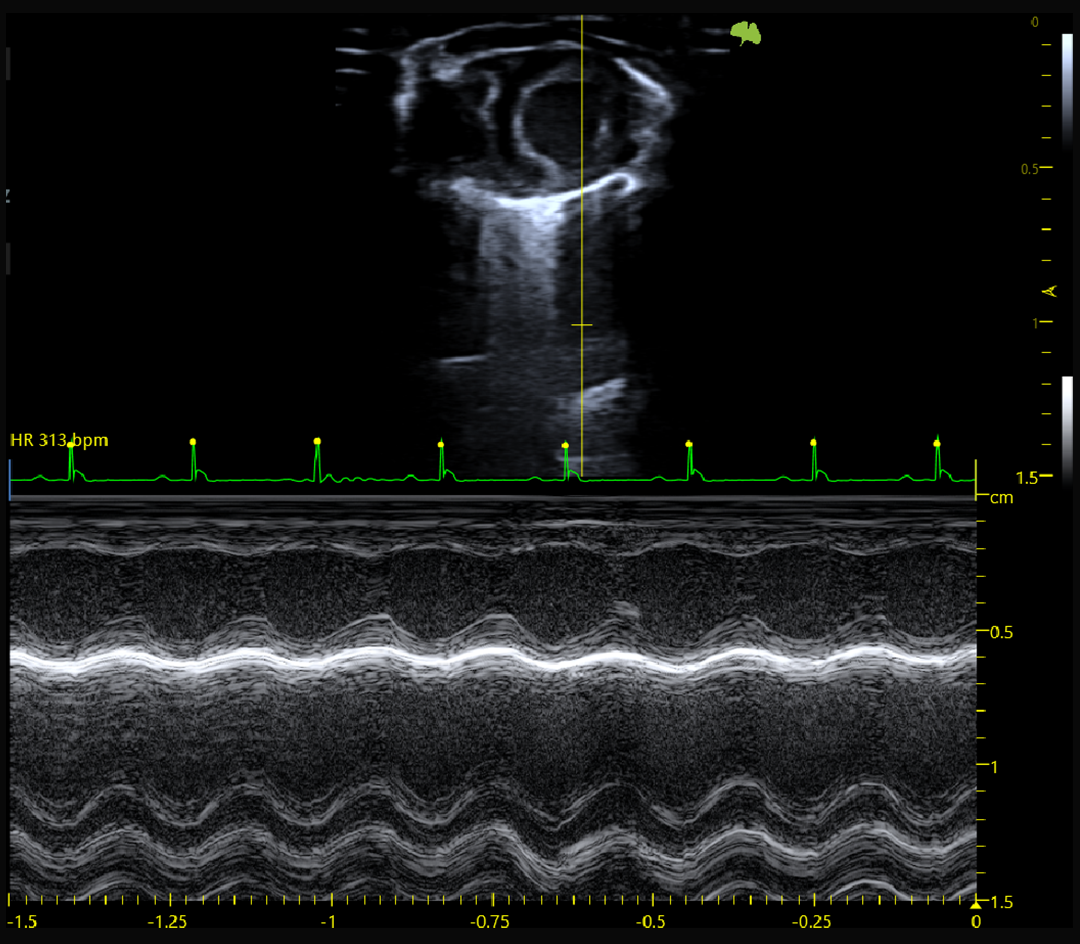

B-mode, M-mode

M-mode précis pour l’analyse fonctionnelle cardiaque

Fonction systolique et diastolique

Imagerie cardiaque haute cadence chez la souris et le rat

ECG intégré